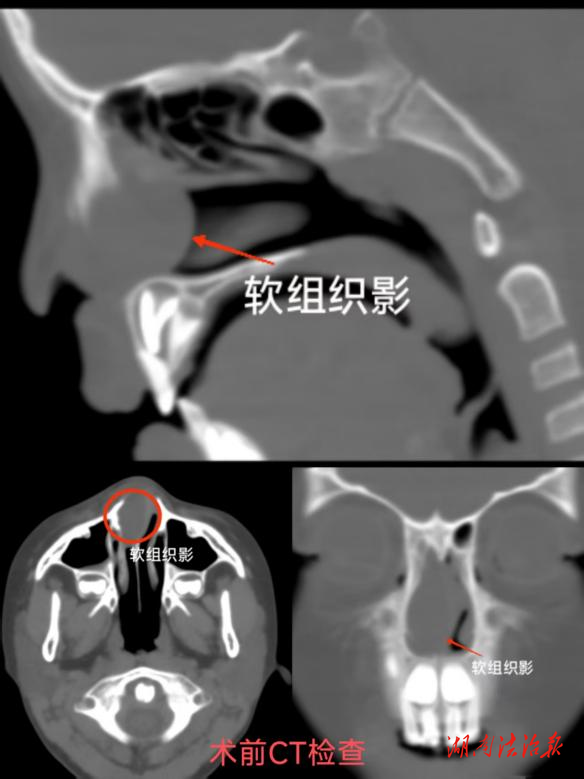

湖南法治报讯(通讯员韦兵)近日,5岁患儿小周因无故出现右侧鼻面部肿痛伴发热、精神萎靡、食欲不振等症状,来到了怀化市中医医院儿科就诊。完善鼻部CT检查后,显示右侧鼻腔软组织堵塞,考虑囊肿可能性大,遂联系耳鼻喉头颈外科进行会诊。

由于患儿害怕检查完全不配合,所以鼻腔内的情况无法窥见。经抗炎等药物保守治疗两天后,病情未见好转,与家属充分沟通后,进行了手术治疗。术中发现,患儿右侧鼻腔见大量玻璃胶样异物,鼻中隔压迫左偏,取出异物后发现周围粘膜糜烂渗血,彻底止血后手术顺利结束。家属看异物后甚是惊讶,竟然是“海绵宝宝”水晶!